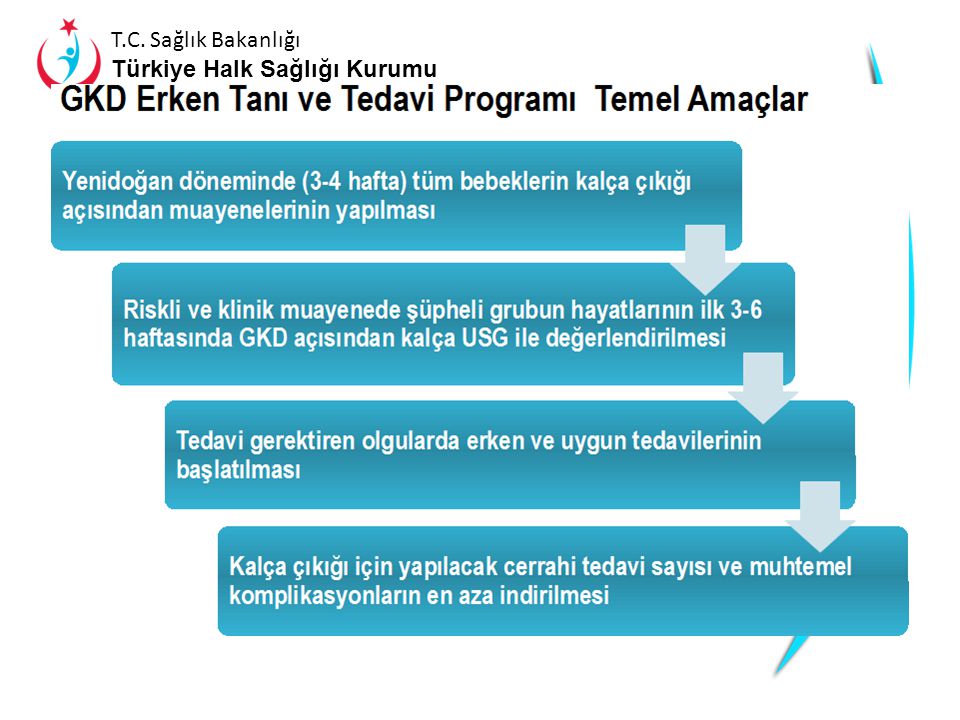

Gelişimsel Kalça Displazisinde ortopedik yaklaşımın ana amacı erken tanı koymak ve bu sayede basit ve yan etkileri sınırlı tedaviler ile sorunu...